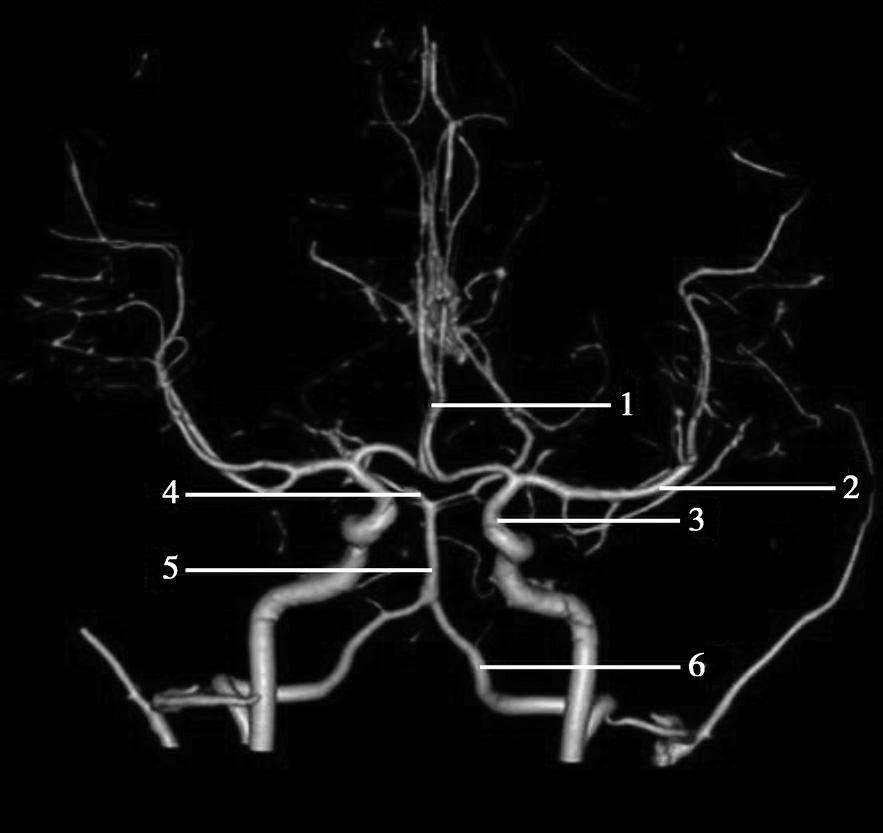

CT血管成像(CT angiography,CTA及CT venography,CTV)通过三维重建技术可显示颅内动静脉的走行、血管壁及血管周围等情况(图1-2-73~图1-2-75)。

图1-2-73 正常颅脑CTA

1.大脑前动脉;2.大脑中动脉;3.颈内动脉;4.大脑后动脉;5.基底动脉;6.椎动脉

大脑动脉环又称Willis环,为连接大脑两半球前部循环及椎基底系统的大吻合环,呈多边形,由下列结构组成:两条大脑前动脉(ACA)交通前段(A 1 ),两侧大脑后动脉(PCA)交通段(P 1 ),两侧颈内动脉(ICA)末端,前交通动脉(ACoA),两侧后交通动脉(PCoA),两侧ICA在脑底通过ACoA相通,并且借PCoA与椎基底动脉系统相通(图1-2-86)。

图1-2-86 正常大脑动脉环

1.左侧大脑前动脉(ACA)交通前段(A 1 );2.前交通动脉(ACoA);3.右侧大脑前动脉(ACA)交通前段(A 1 );4.右侧后交通动脉(PCoA);5.左侧后交通动脉(PCoA);6.左侧大脑后动脉(PCA)交通段(P 1 );7.右侧大脑后动脉(PCA)交通段(P 1 )

大脑动脉环小而重要的穿支血管给许多重要结构供血,如垂体柄、垂体腺、丘脑、下丘脑视神经交叉、视神经、视束、基底节及中脑。对于闭锁性血管疾病,大脑动脉环是侧支血流最充分的供血来源,熟知其正常解剖、变异与异常十分必要。